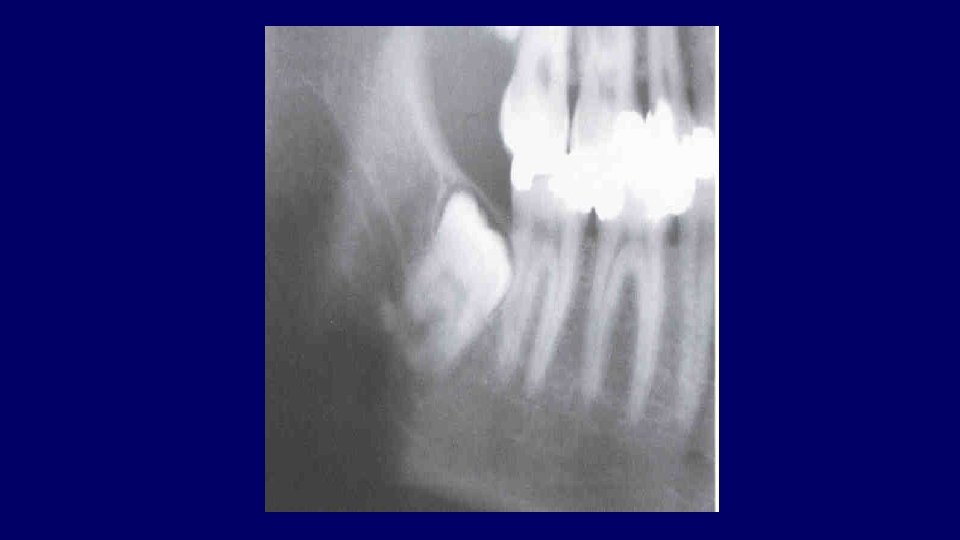

Mandibular third molar assessment (1) Type of impaction (2) Depth of impaction (3) Root pattern (4) Crown form (5) Bone density (6) Relationship to ID nerve (7) Caries (8) Position and root pattern of 2 nd molar (9) Associated pathology (10)Access

Types of impaction • Vertical • Mesioangular • Distoangular • Horizontal • Transverse

(2) Depth of impaction

Pell & Gregory Classification • Based on the amount of tooth covered by the anterior border of the ramus • The depth of the impaction relative to the adjacent tooth

Pell & Gregory • Depth of Impaction – Mandibular Class A Class B Class C